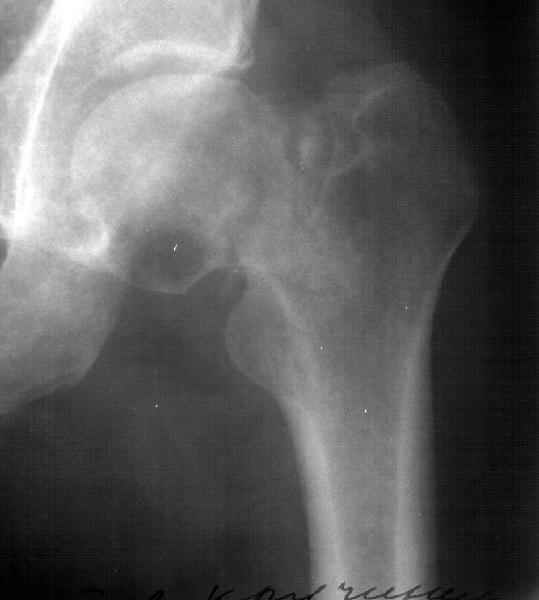

Уважаемый Александр! По 38-летнему пациенту. На томограмме имеются явные признаки асептического некроза. Этот процесс будет развиваться стремительно.

1-2 года и Вы вынуждены будете эндопротезировать пациента. Есть ли необходимость в дополнительной операции (остеотомии)? У 35-летнего пациента

альтернативы нет. Протез. АИФ.

Коль скоро функция сустава сохранена, я бы не торопился с эндопротезированием у 38 летнего пациента.

Рентгенологические признаки пост травматического аваскулярного некроза по классификации Ficat / Arlet Stage 1. на мой взгляд DHS - без какой -либо остеотомии стабилизировало зону перелома, а сам процесс рассверливания шейки бедра съимитировал бы так называемую core decompression procedure, которая показана при 1-3 стадиях AVN.

You have a non union neck, avascualr necrosis and varus deformity.

Inspite of the avascular necrosis it is still wothwhile to get the femur neck united.